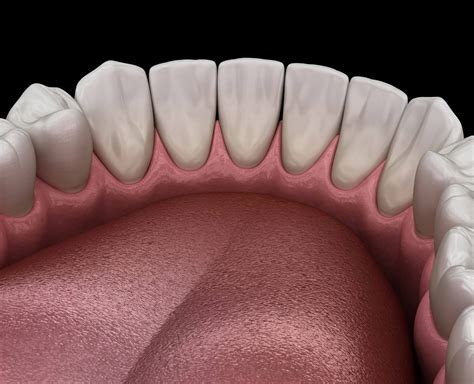

Torus mandibularis refers to a bony outgrowth, or exostosis, that develops along the lingual aspect (the side near the tongue) of the mandible, or lower jawbone. These growths are essentially dense, cortical bone covered by a thin layer of mucosal tissue. When browsing Torus Mandibularis images, you will typically observe that they appear as rounded, hard, and sometimes lobulated projections located above the mylohyoid line, usually in the area of the premolars.

Identifying these growths involves understanding their physical properties. Because they are composed of healthy, dense bone, they feel rock-hard to the touch and are immobile, as they are part of the jawbone itself. Here are the primary characteristics often depicted in Torus Mandibularis images:

• Location: Typically found on the lingual (tongue) side of the lower jaw, most commonly near the premolar teeth.

• Consistency: Extremely hard to the touch; they do not feel soft, spongy, or fluid-filled.

• Surface Texture: Can be smooth, nodular, or irregular in shape.

• Symmetry: Very often, they appear bilaterally, meaning they are present on both the left and right sides of the jaw.